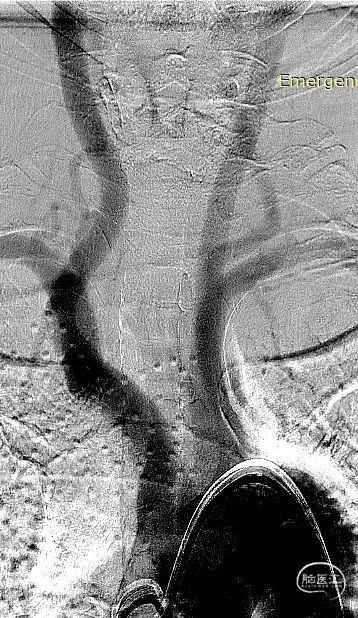

术前CT

术前DSA、DSA 3D

该病例为右侧后交通段绝对宽颈动脉瘤,动脉瘤体7.2mm*6.7mm*5.7mm,瘤体上多个小子囊,载瘤动脉异常扭曲,直径约4.2mm,工作角度难以选择;另外患者高龄,颈内动脉扭曲且不规则狭窄,因此对支架导管的输送性和支架的贴壁性要求较高。且患者动脉瘤存在多个小子囊,填塞后子囊不显影才能降低再出血风险。手术策略是三导管技术(两根弹簧圈微导管分别放入子囊和大的瘤腔、一根支架导管)。